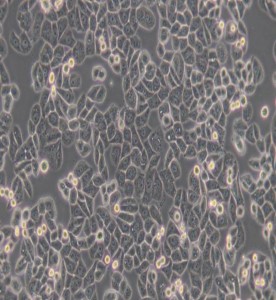

MDA-MB-468人乳腺癌細胞(L15)

細胞形態 : 上皮細胞樣

生長特性 : 貼壁細胞